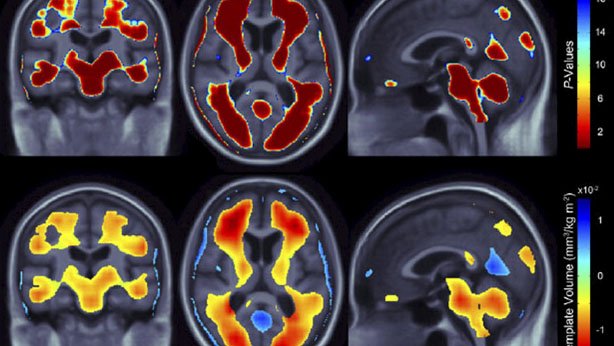

Está disponível no site da Rádio e Televisão da Unicamp (RTV) o programa Pesquisa em Pauta com o tema “Como funciona o cérebro na obesidade”. A obesidade tornou-se nos últimos anos um dos principais problemas de saúde pública no mundo. Trata-se de uma condição que associada a doenças como diabetes, arteriosclerose, hipertensão arterial e alguns tipos de câncer reduzem a qualidade e a expectativa de vida das pessoas.

Neste programa, o professor Licio Augusto Velloso, da Faculdade de Ciências Médicas da Unicamp e a pesquisadora Gabriela de Souza mostram os mecanismos pelos quais a dieta consumida atualmente por muitas pessoas no planeta favorece o desenvolvimento da obesidade. Abordam também as formas de evitar que isto aconteça e as perspectivas futuras para o tratamento. (veja o link)